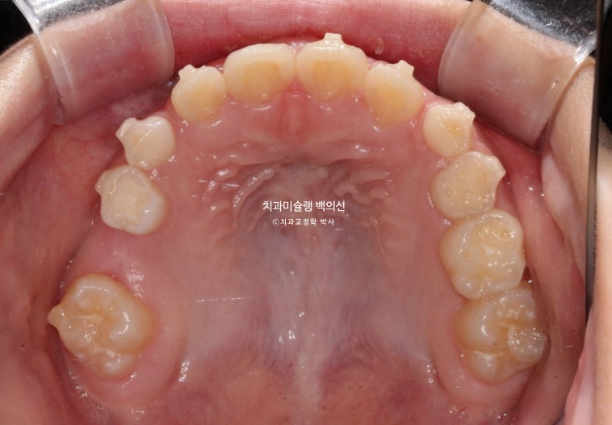

2025.5 드디어 치료를 마무리 했습니다.

중심선은 잘 맞으며

그사이 남은 유치들이 대거 빠지고 영구치 맹출을 기다리는 중입니다.

영구치가 다 나올때까지 유지는 뺏다꼈다 하는 가철식 유지장치를 사용키로 합니다.

아이가 아직 성장중인 만큼 꼼꼼한 사후관리가 필요합니다.

총 치료기간은 프리올소 2개월, 인비절라인 퍼스트 2년입니다.

성장을 이용한 비대칭 치료이니만큼, 최대성장기를 최대한 이용하기 위해 중간에 쉬는시간 없이 인비절라인퍼스트가 보증하는 보증기한동안 장치를 계속 착용했습니다.

비대칭은 개선되었으며 중심선은 맞아졌습니다.

앞니 교합은 좋습니다.